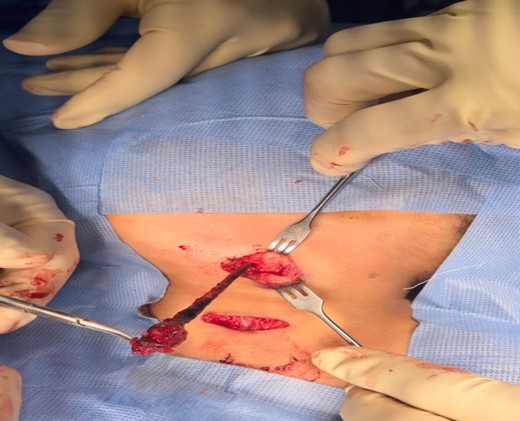

After draping and sterilisation, the small left-sided neck punctum was identified, probing of the fistula tract by a lacrimal probe was done, followed by the insertion of an arterial catheter inside the fistula tract (Fig. 6). The amount of methylene blue added was 0.01 ml per 2 ml of fibrin glue, and a total of 4 ml of this mixture was injected. This mixture allows the glue to be dyed adequately and does not inhibit its solidification. The arterial catheter was totally inserted, about 7 cm in length, and injection of methylene blue with fibrin glue was performed using an arterial catheter inside the tract. An elliptical incision was made around the fistula opening, followed by dissection of the tract. The tract was obvious, firm and colored with methylene blue. The tract was easily dissected without the need to remove extra tissues around it. Another superior incision, a step ladder incision, was made as the tract was long. The tract followed to its entry into the tonsillar fossa, which was ligated. The internal carotid artery, internal jugular vein, hypoglossal nerve and glossopharyngeal nerve were all identified and preserved. Bilateral tonsillectomy was performed, and the tract was visualised within the left tonsil (Figs 1–4). The left tract at the tonsillar bed after the tonsillectomy was ligated and cauterised. Then bilateral auricular sinus excision is done. The patient was then seen after 3 months of surgery and was doing well.

The left tonsill after removal and tract opening seen clearly on its surface.